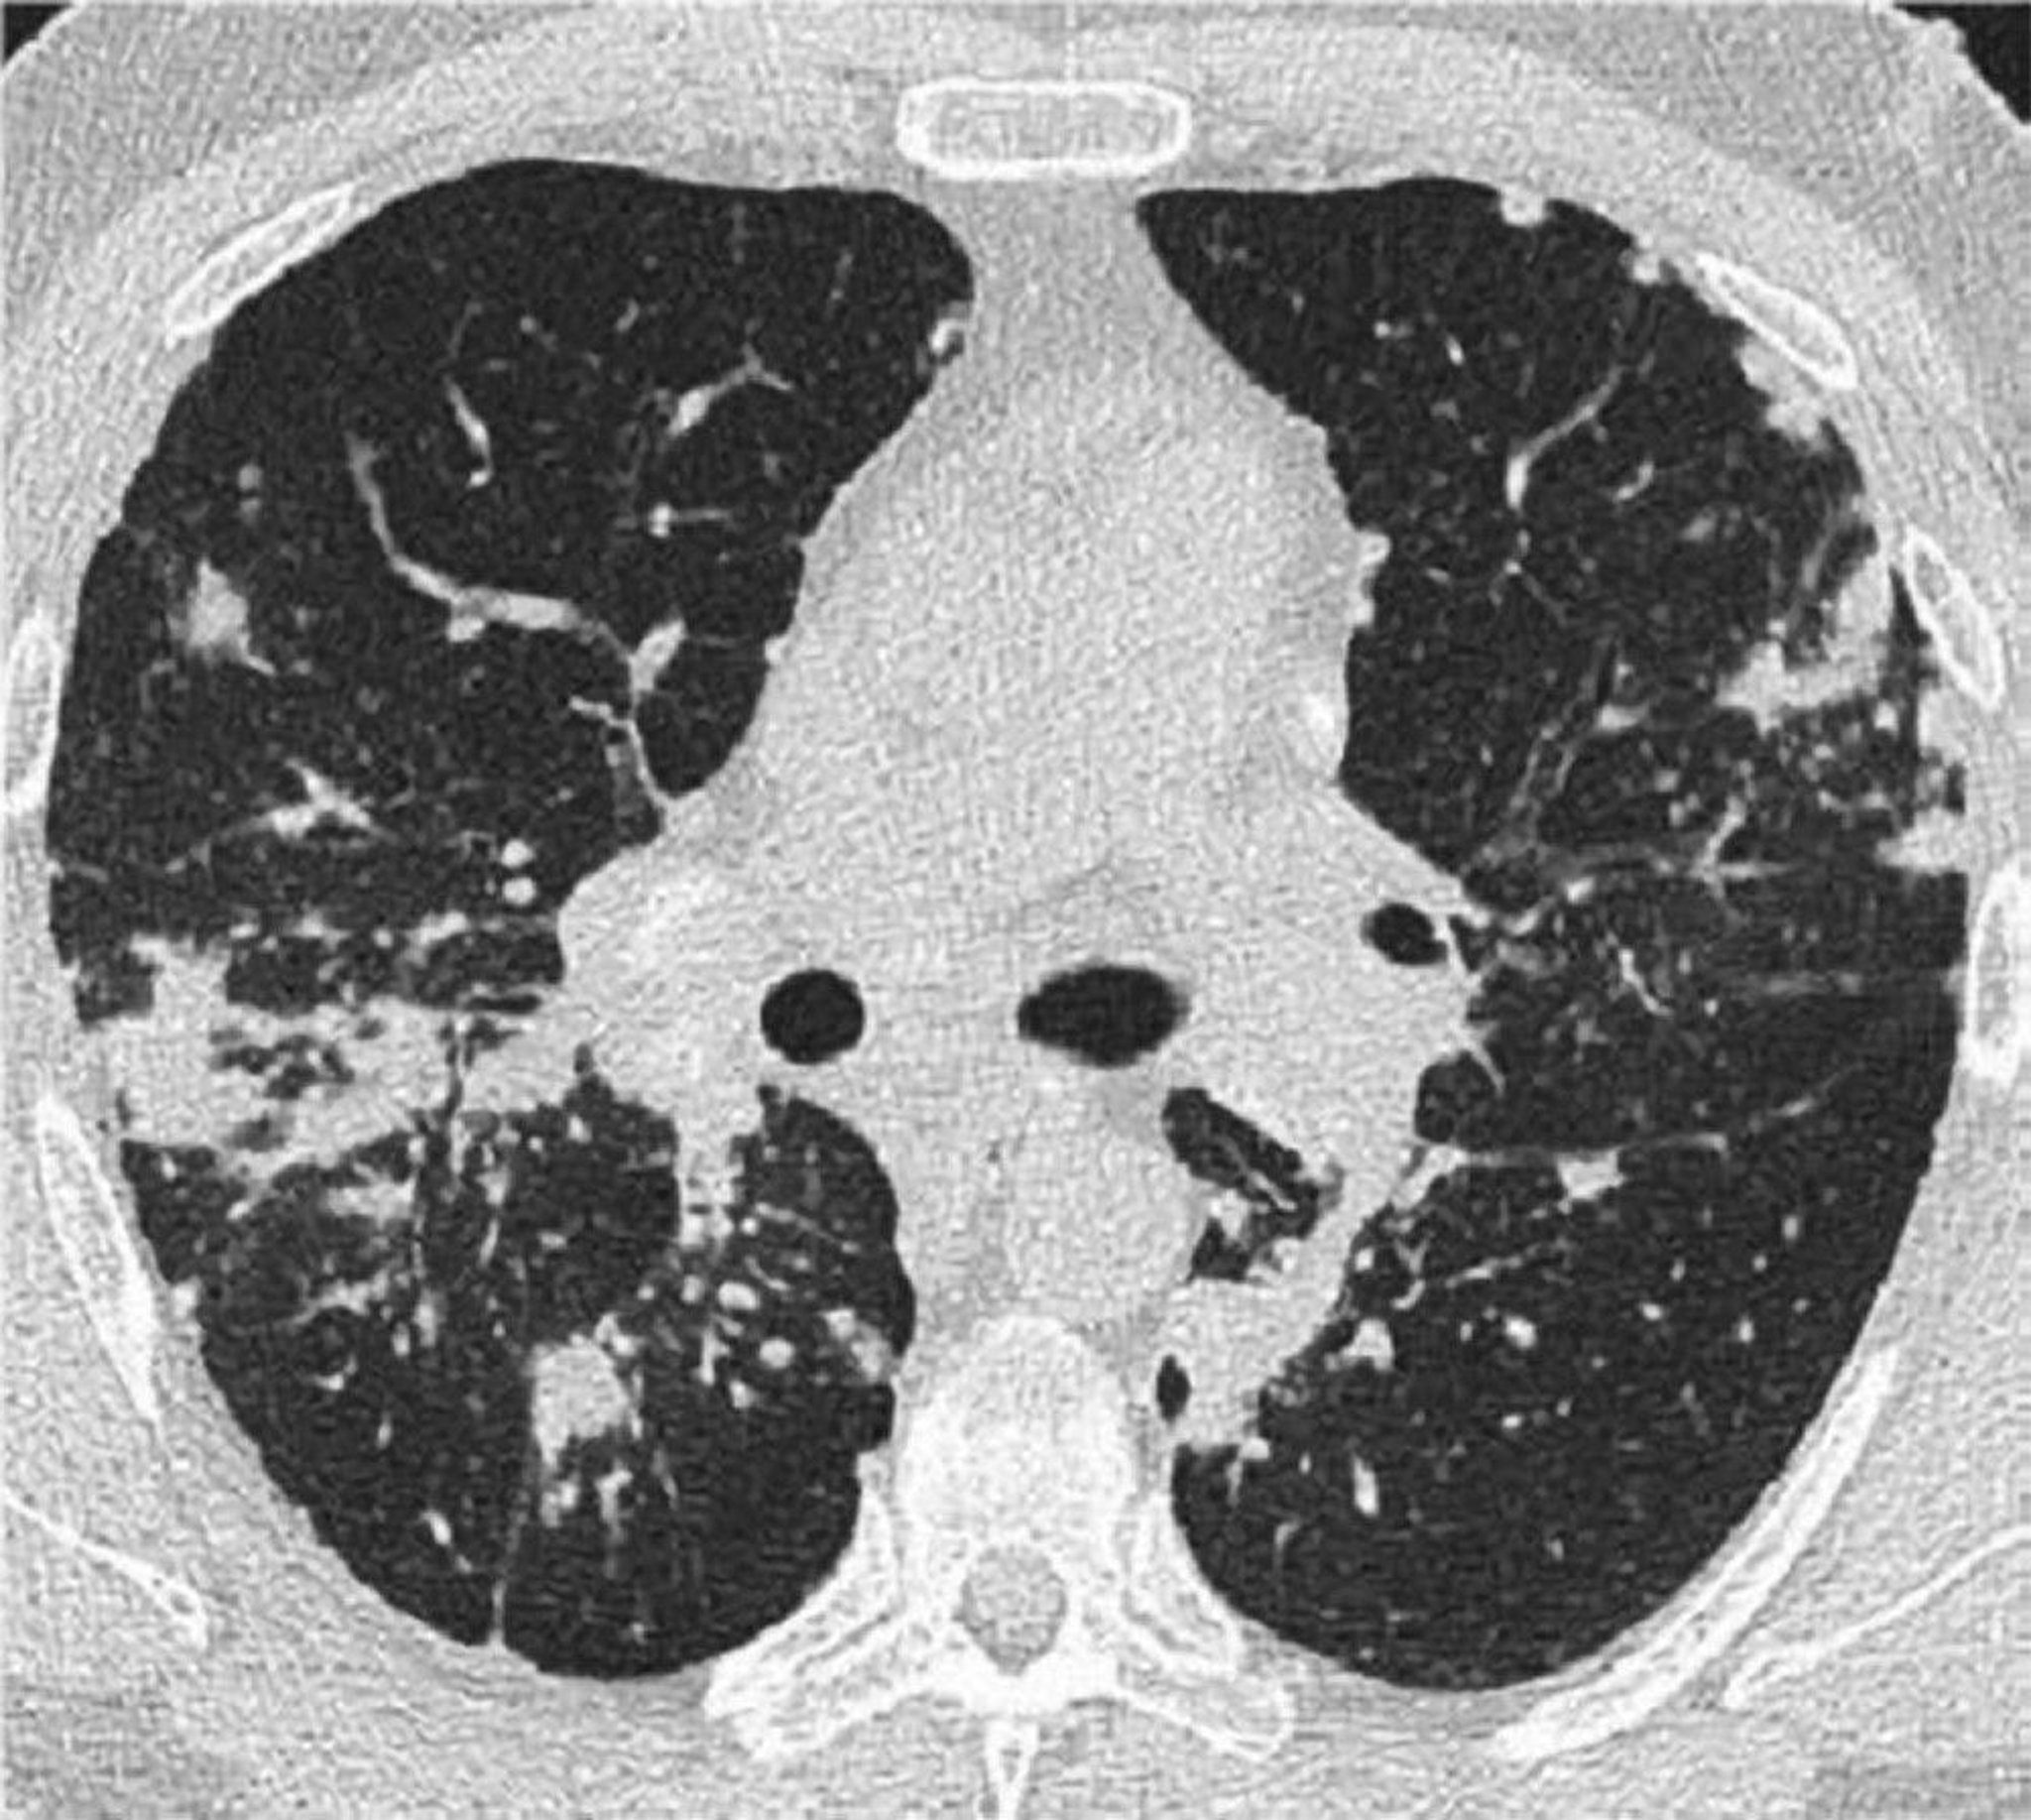

Chest CT Scan in Pulmonary Sarcoidosis

This high-resolution CT of the chest of a patient with pulmonary sarcoidosis shows thickening of the bronchovascular bundles and beading of the interlobular septa.

Image courtesy of Birendra P. Sah, MD, FCCP.